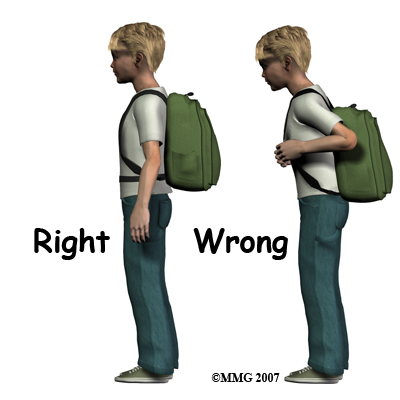

Carrying backpacks may sometimes be to blame for non-specific back pain. Your physical therapist will discuss this with your child and may ask to see the backpack that your child regularly uses. Many children these days carry extremely heavy backpacks and use backpacks that are poorly designed ergonomically. It is suggested that children wear their backpack using both shoulder straps and that if there is a waist or chest strap, that these straps also be used. When purchasing a backpack, ensure the shoulder straps are wide, padded, and adjustable so that the weight can be evenly distributed. As a general rule backpacks should not be heavier than 10% of your child’s body weight. Making more frequent trips to the locker can decrease the weight of the backpack, and packing the backpack so the weight is distributed evenly can also decrease the strain on the back. Using a wheeled backpack may be an option and should be considered if your child suffers from frequent back pain, or is recovering from an injury.

Carrying backpacks may sometimes be to blame for non-specific back pain. Your physical therapist will discuss this with your child and may ask to see the backpack that your child regularly uses. Many children these days carry extremely heavy backpacks and use backpacks that are poorly designed ergonomically. It is suggested that children wear their backpack using both shoulder straps and that if there is a waist or chest strap, that these straps also be used. When purchasing a backpack, ensure the shoulder straps are wide, padded, and adjustable so that the weight can be evenly distributed. As a general rule backpacks should not be heavier than 10% of your child’s body weight. Making more frequent trips to the locker can decrease the weight of the backpack, and packing the backpack so the weight is distributed evenly can also decrease the strain on the back. Using a wheeled backpack may be an option and should be considered if your child suffers from frequent back pain, or is recovering from an injury.

Carrying backpacks may sometimes be to blame for non-specific back pain. Your physical therapist will discuss this with your child and may ask to see the backpack that your child regularly uses. Many children these days carry extremely heavy backpacks and use backpacks that are poorly designed ergonomically. It is suggested that children wear their backpack using both shoulder straps and that if there is a waist or chest strap, that these straps also be used. When purchasing a backpack, ensure the shoulder straps are wide, padded, and adjustable so that the weight can be evenly distributed. As a general rule backpacks should not be heavier than 10% of your child’s body weight. Making more frequent trips to the locker can decrease the weight of the backpack, and packing the backpack so the weight is distributed evenly can also decrease the strain on the back. Using a wheeled backpack may be an option and should be considered if your child suffers from frequent back pain, or is recovering from an injury.

Carrying backpacks may sometimes be to blame for non-specific back pain. Your physical therapist will discuss this with your child and may ask to see the backpack that your child regularly uses. Many children these days carry extremely heavy backpacks and use backpacks that are poorly designed ergonomically. It is suggested that children wear their backpack using both shoulder straps and that if there is a waist or chest strap, that these straps also be used. When purchasing a backpack, ensure the shoulder straps are wide, padded, and adjustable so that the weight can be evenly distributed. As a general rule backpacks should not be heavier than 10% of your child’s body weight. Making more frequent trips to the locker can decrease the weight of the backpack, and packing the backpack so the weight is distributed evenly can also decrease the strain on the back. Using a wheeled backpack may be an option and should be considered if your child suffers from frequent back pain, or is recovering from an injury.